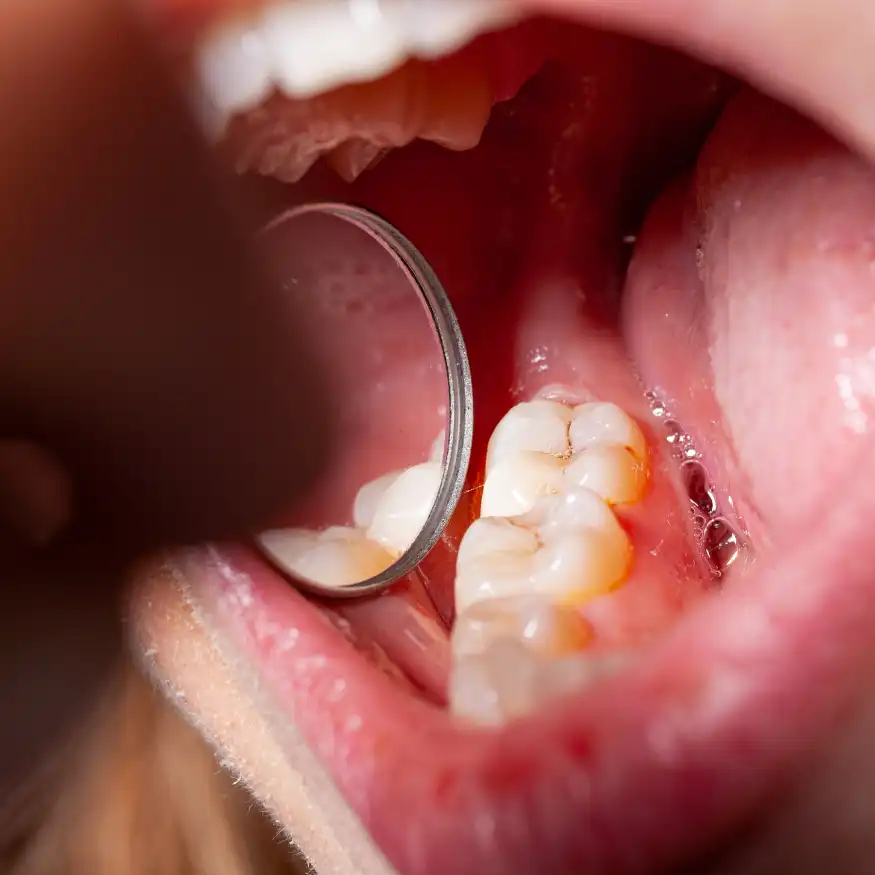

Restauraciones en Resina Compuesta

Este tratamiento está diseñado para reparar y restaurar dientes dañados o deteriorados por caries, traumatismos o desgaste natural, utilizando resina compuesta de alta calidad que se adhiere perfectamente a la estructura dental. La resina está disponible en una variedad de tonos, permitiendo que el color se combine con el diente natural para lograr un aspecto estético y natural.

Beneficios

Además de restaurar la funcionalidad del diente, la resina compuesta es menos invasiva que otros métodos, conservando más tejido natural. Proporciona una solución duradera, resistente a la presión de la masticación y con una estética impecable, lo cual es ideal tanto para dientes visibles como para molares.

Proceso

Tras una evaluación inicial, se limpia y prepara la cavidad dental. La resina se aplica en capas, moldeando y esculpiendo el material para adaptarse a la forma original del diente. Luego se endurece con luz especial y se pule para una apariencia lisa y brillante.